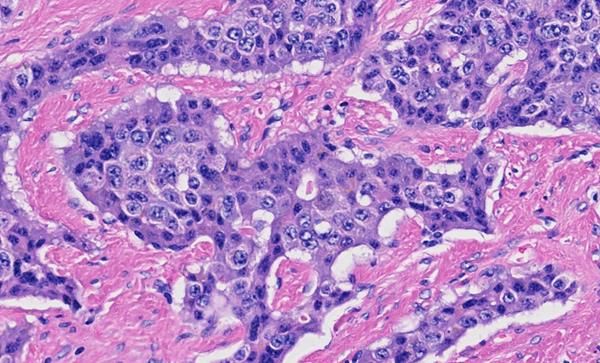

A generational advancement in digital pathology, Pramana’s family of scanners is a modular system of imaging and workflow solutions that is able to process a wide range of specimens using real-time AI algorithms to optimize efficiency, reduce costs, and enhance safety during the scanning process.

Healthcare providers, research labs, molecular science companies, and academic institutions are now digitizing millions of slides each day. Pramana’s innovation and capabilities complement and expand the technologies Evident can provide to keep pace with daily caseloads, automate quality control, seamlessly integrate data and communication systems, and take advantage of the industry’s newest advances in AI-driven imaging and analysis.

Pramana is a health tech company accelerating the adoption of digital pathology across labs, hospitals, clinics, and medical centers. With Pramana’s AI-powered imaging solution, pathologists achieve industry-leading image quality and unprecedented accuracy.

Built-in AI algorithms and automated quality control eliminate up to 70% of manual workflow steps while capturing previously undetectable tissue features, radically improving clinical diagnostics and research.